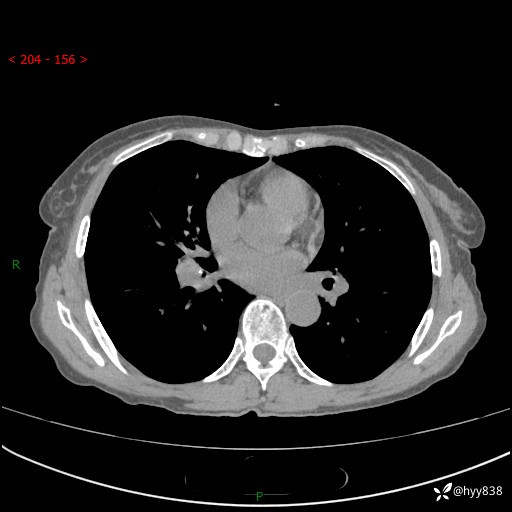

患者性别:男

患者年龄:69岁

简要病史:咳嗽咳痰2月,夜间加重

临床诊断:感染

胸部CT平扫